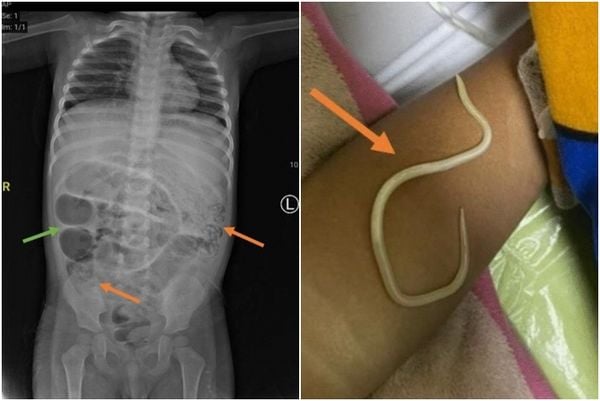

(雅加达12日综合电)印尼一名3岁男童连续3天腹胀无法排便,而且开始发烧,父母带他就医检查时,赫然发现孩子体内挤满了数十条蛔虫,而且住院期间还呕吐出虫。医疗团队后来决定替男童动手术,把体内大量蛔虫取出。

《每日邮报》报导,医生初时诊断男童便秘,可是男童隔日呕吐时却吐出虫子,院方连忙照了胃部X光,发现他体内状况有异,决定动手术,结果发现大量蛔虫阻塞他的小肠3处不同区域。

医疗团队在他的小肠切开一个小口,透过轻轻挤压的方式,把蛔虫挤出来,接著再把伤口缝合,并把蛔虫送检。